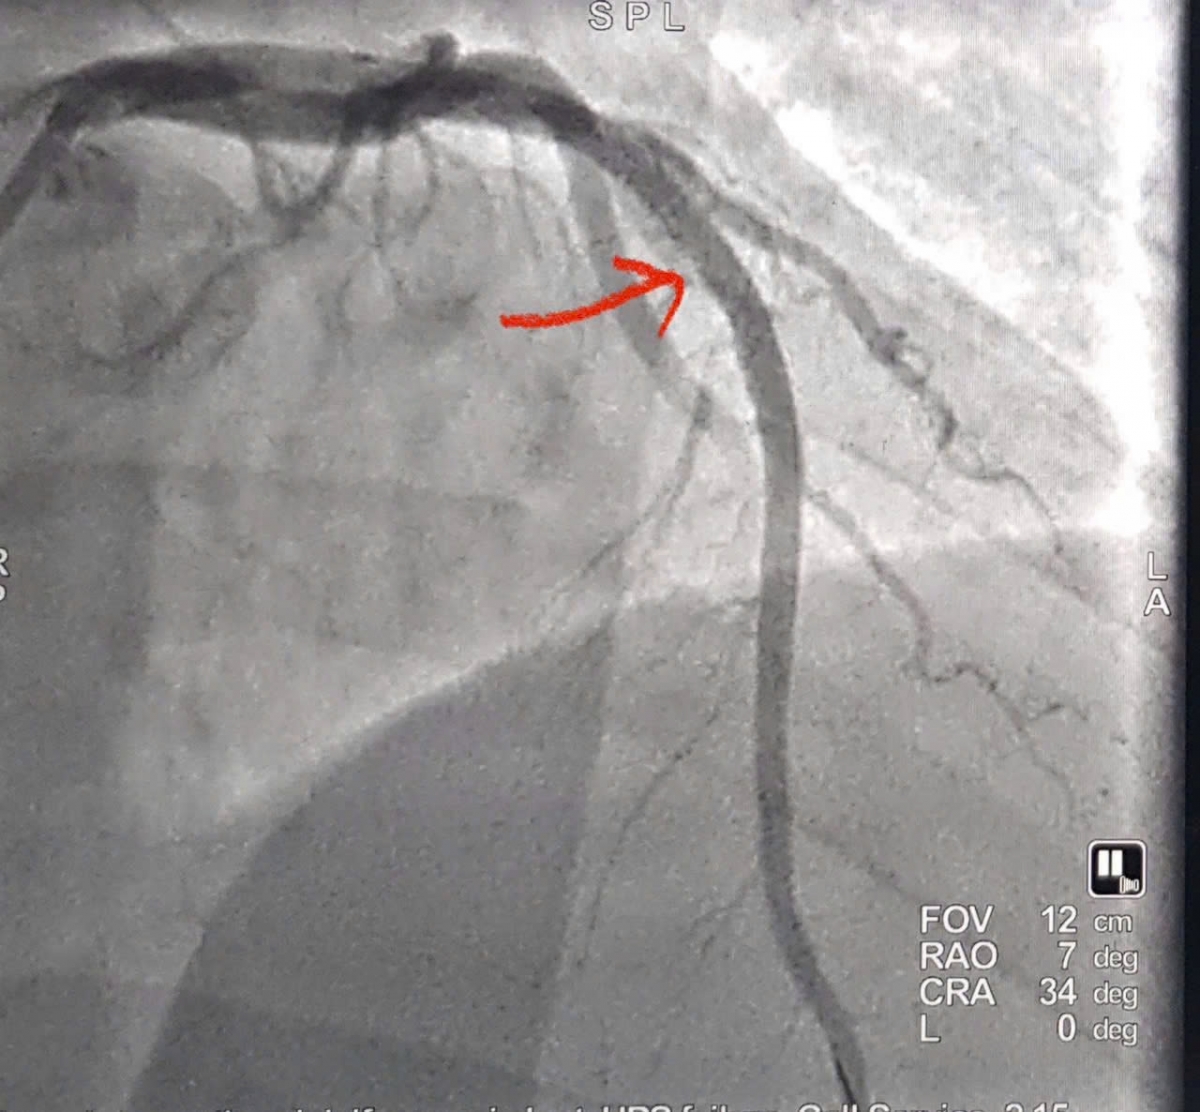

Hình ảnh tắc động mạch liên thất trước đoạn 2 (LADII) (Hình mũi tên đỏ) khi nhập viện tại Bệnh viện đa khoa Nghệ An

Bệnh nhân được chỉ định chụp động mạch vành cấp cứu bằng hệ thống chụp mạch số hóa xóa nền (DSA) qua đường động mạch quay phải – phương pháp hiện đại, ít xâm lấn, giúp rút ngắn thời gian can thiệp và giảm biến chứng.

Kết quả chụp cho thấy tắc hoàn toàn động mạch liên thất trước đoạn II (LAD II) – nhánh mạch vành quan trọng nuôi phần lớn cơ tim thất trái. Ê-kíp can thiệp đã nhanh chóng tiến hành nong bóng và đặt một stent phủ thuốc tại vị trí tổn thương. Sau can thiệp, dòng máu được tái lập ngay, cải thiện rõ rệt tình trạng thiếu máu cơ tim.